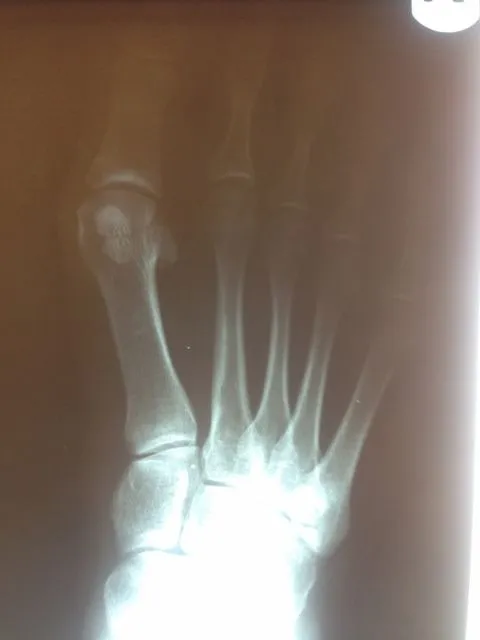

Before and immediately postop S/P bunionectomy

Before and 6 months status post bunionectomy.